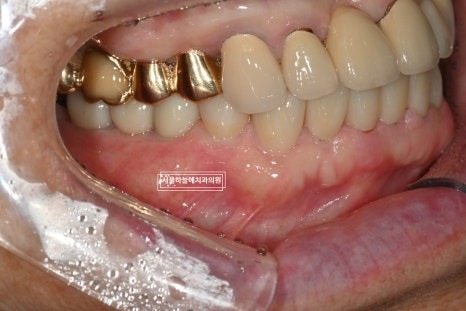

처음 내원 시 상태

처음 내원 당시 엑스레이와 구강 상태를 보면

앞니는 파절되어 있었고

아래 어금니가 없는 기간이 길어

위 치아와 잇몸이 맞닿을 정도로 공간이 부족,

아래 앞니 역시 심하게 마모된 상태였습니다.

이러한 경우에는

단순히 임플란트만 심는 것이 아니라

교합(위아래 맞물림) 전체를 고려한

치료 계획이 필요합니다.